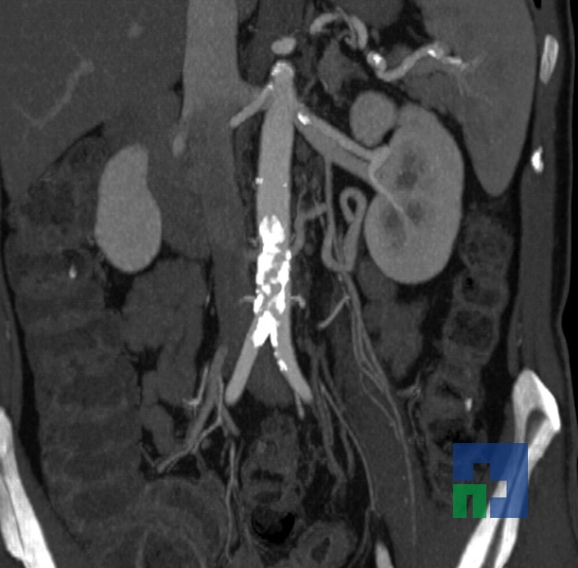

- Accidentelor vasculare cerebrale ischemice sau hemoragice

- Fistula carotido-cavernoasa